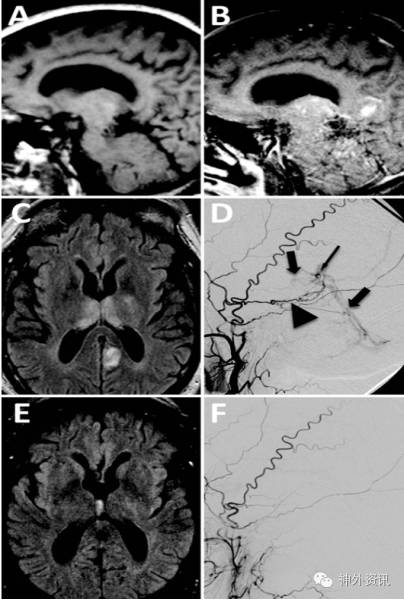

4例患者均为男性,53岁~71岁;症状为记忆功能紊乱和恶化,或智能转换状态改变,于发病后4天至6个月入院。入院时检查,有短期和长期记忆力下降、注意力不能集中、联想面孔失认症、中或重度语言流畅性障碍、理解力降低及情绪不稳。其中1例伴轻微的左侧肢体无力。Kokmen短期简易智能状态量表评分为24/30、30/38不等。MRI影像学检查,T1加权像矢状位增强扫描显示双侧丘脑强化,FLAIR像显示双侧丘脑内侧高信号。DSA示半球深部dAVF,深静脉引流(图1)。1例评定为改良Borden-Shucart分型2S,3例评定为改良Borden-Shucart分型3S。2例行血管内介入栓塞治疗,2例血管内介入栓塞结合手术治疗。治疗后患者的影像学异常和临床症状很快缓解。1例术后3月死于心脏病;其余随访3个月至6个月,Kokmen短期简易智能状态量表评分恢复正常、或达30/30、和34/38;1例术前有轻微肢体无力者症状消失。

图1. A.颅脑MRI-T1加权矢状位像平扫显示无异常信号;B.颅脑MRI-T1加权矢状位增强像扫描示丘脑强化;C.FLAIR像显示双侧丘脑内侧高信号;D.左侧颈外动脉造影提示颅内深部dAVF,深静脉引流;E.血管内介入栓塞6周后,MRI-FLAIR像显示双侧丘脑高信号消失;F.左颈外动脉造影示dAVF完全栓塞。